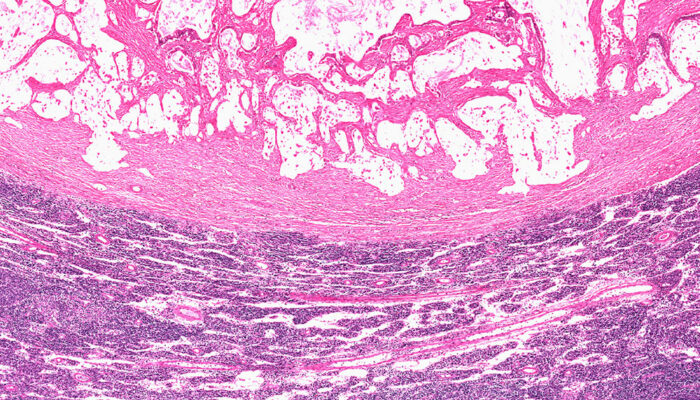

The condition, characterized by a malignant tumor, begins in the nerve cells of the digestive system. With time, they mutate and affect the normal functioning of the cells in the organ. Patients experience symptoms like anemia, abdominal pain, and vomiting, and these further aggravate if the condition is not treated. Therefore, ensure that you consult your doctor at the earliest.